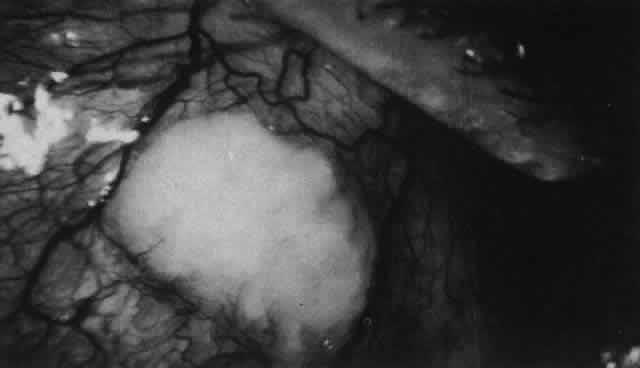

In contrast to simple episcleritis, the infiltration and edema of nodular episcleritis are localized to one part of the globe, forming a nodule and some surrounding congestion (Color Plate 1B). The nodule can be moved over the underlying sclera, which is not edematous. The scleral plexus of vessels can be distinguished deep to the nodule, lying flat on the sclera and slightly congested but otherwise normal in color and configuration (Figs. 15 and 16). Episcleral nodules may be single or multiple but do not undergo necrosis (see Fig. 16). After multiple attacks of nodular episcleritis in the same location, the superficial lamellae of the sclera show some alteration and become slightly more transparent in this one area.

Fig. 16. Deep vessels, which are normal in configuration, can be traced beneath edematous nodules lying flat on the sclera. (Watson PG: Connective tissue disorders and the eye. In: Recent Advances in Ophthalmology, Vol 5, pp 214–277. London, Churchill-Livingstone, 1975)